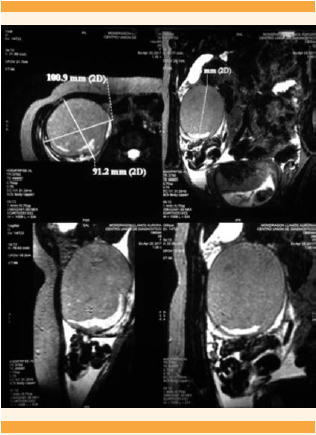

Paciente de 29 años, que acudió al servicio de Urgencias Ginecoobstétricas del Hospital General Dr. Miguel Silva de Morelia, Michoacán, con embarazo de 15.2 semanas (estimado por fecha de la última menstruación) y dolor pélvico agudo de 3 horas de evolución, localizado en la fosa iliaca derecha, que se irradiaba al hipocondrio derecho, incapacitante, calificado en la escala visual análoga de 9. Antecedentes personales patológicos, quirúrgicos, traumáticos, alérgicos, transfusionales y toxicomanías negados. Antecedentes ginecoobstétricos: menarquia a los 14 años, ciclo menstrual 28/4, eumenorreica a expensas de útero gestante; prueba de embarazo positiva; 5 embarazos, 3 partos y 1 aborto. Inicio de la vida sexual activa a los 18 años, una pareja sexual, sin implementación de métodos anticonceptivos; Papanicolaou nunca realizado. Durante la exploración física se encontró con abdomen semigloboso y en la auscultación peristalsis normal. A la palpación media y profunda se percibió resistencia muscular, dolor en la fosa iliaca y hemiabdomen derechos, con signo de rebote positivo en la fosa iliaca derecha; no se palparon visceromegalias ni tumoraciones. A la exploración genital se encontró con cérvix posterior desplazado hacia la izquierda, de consistencia dura, cerrado, dolor a la movilización referido hacia el lado derecho, sin sangrado activo, cavidad vaginal eutérmica. Al tacto bimanual: fondo de saco lateral derecho ocupado por una tumoración de consistencia dura, móvil, doloroso a la movilización, tumoración no delimitada. El ultrasonido abdomino-pélvico reportó un embarazo intrauterino, con feto único, vivo, de 14.2 semanas (estimadas por fetometría), con 140 lpm y placenta normoinserta. También se observó una imagen ovoide, delimitada, de contenido heterogéneo, con imágenes hipodensas en su interior correspondientes a grasa, además de imágenes hiperecogénicas con sombra acústica relacionadas con calcificaciones. A pesar de los hallazgos detectados en el estudio de imagen, no se concluyó la situación anatómica, debido al tamaño de la tumoración y el estado gestacional (Figura 1). La resonancia magnética de abdomen superior evidenció una masa anexial bien definida y delimitada, de bordes regulares, de aproximadamente de 10 x 9 x 9.1 cm, quizá asociada con endometrioma (Figura 2).